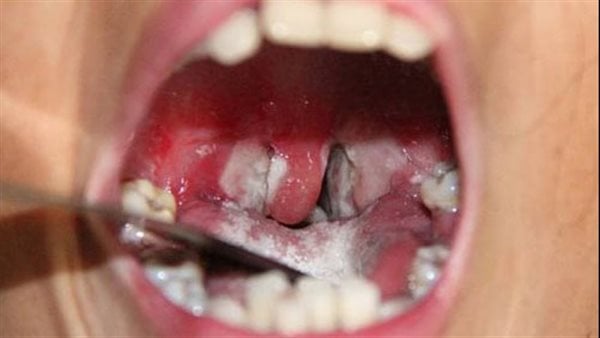

أفادت مصادر محلية ان سبعة أشخاص توفوا ببلدية تناها بمقاطعة كنكوصة في ولاية العصابة، وذلك جراء إصابتهم بمرض يرجح أنه الدفتيريا، فيما أصيب أكثر من 70 آخرين.